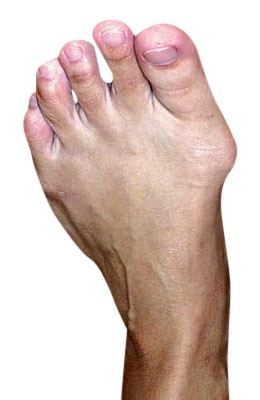

Lapidus Forever Bunionectomy™ and Hammertoe Correction with Tailor's Bunionectomy

Michael had neglected his painful foot for years because he was afraid of surgery and the pain. His condition deteriorated to much that he had a dislocated second toe, a bunion and tailor’s bunion deformity and severe hammertoes. Our foot and ankle surgeons performed extensive surgery on his foot correcting his bunion with a Lapidus Forever Bunionectomy™, relocation of his 2nd and 3rd metatarsal bone with metatarsal osteotomies and plantar plate repairs, hammertoe correction with our revolutionary Ossio implant and a tailor’s osteotomy bunionectomy. Michael was back on his foot 2 weeks after surgery and back in shoes in 8 weeks. He had no post-operative pain of significance and was so grateful that he invited us all to dinner at his restaurant (which was delicious)! The after image taken 12 weeks post-op.